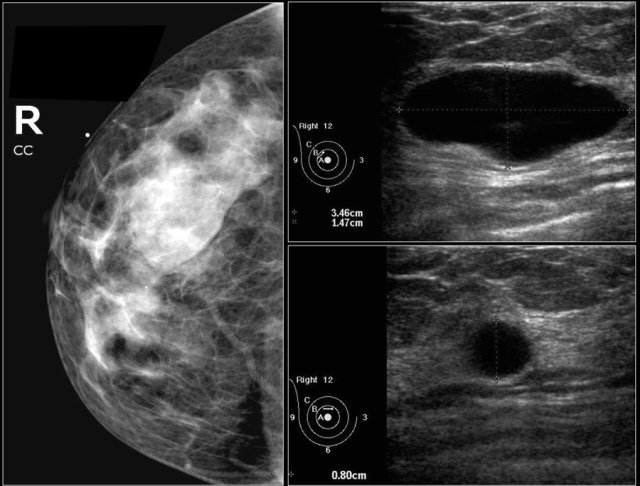

Here a non-palpable sharply defined mass with a group of punctate calcifications.

The mass was categorized as BI-RADS 3.

Continue with follow up images.

- The initial short-term follow-up of a BI-RADS 3 lesion is a unilateral mammogram at 6 months, then a bilateral follow-up examination at 12 months. Assuming stability perform a follow-up after one year and optionally after another year.

- If the findings shows no change in the follow up the final assessment is changed to BI-RADS 2 (benign) and no further follow up is needed.

Follow-up at 6, 12 and 24 months showed no change and the final assessment was changed into a Category 2.

Nevertheless the patient and the clinician preferred removal, because the radiologist was not able to present a clear differential diagnosis.

So add the following sentence in your report:

- BI-RADS 2 (benign finding).

- Instead of stopping the follow-up, tissue diagnosis will be performed, due to patient and referring clinician concern.

PA: benign vascular malformation.